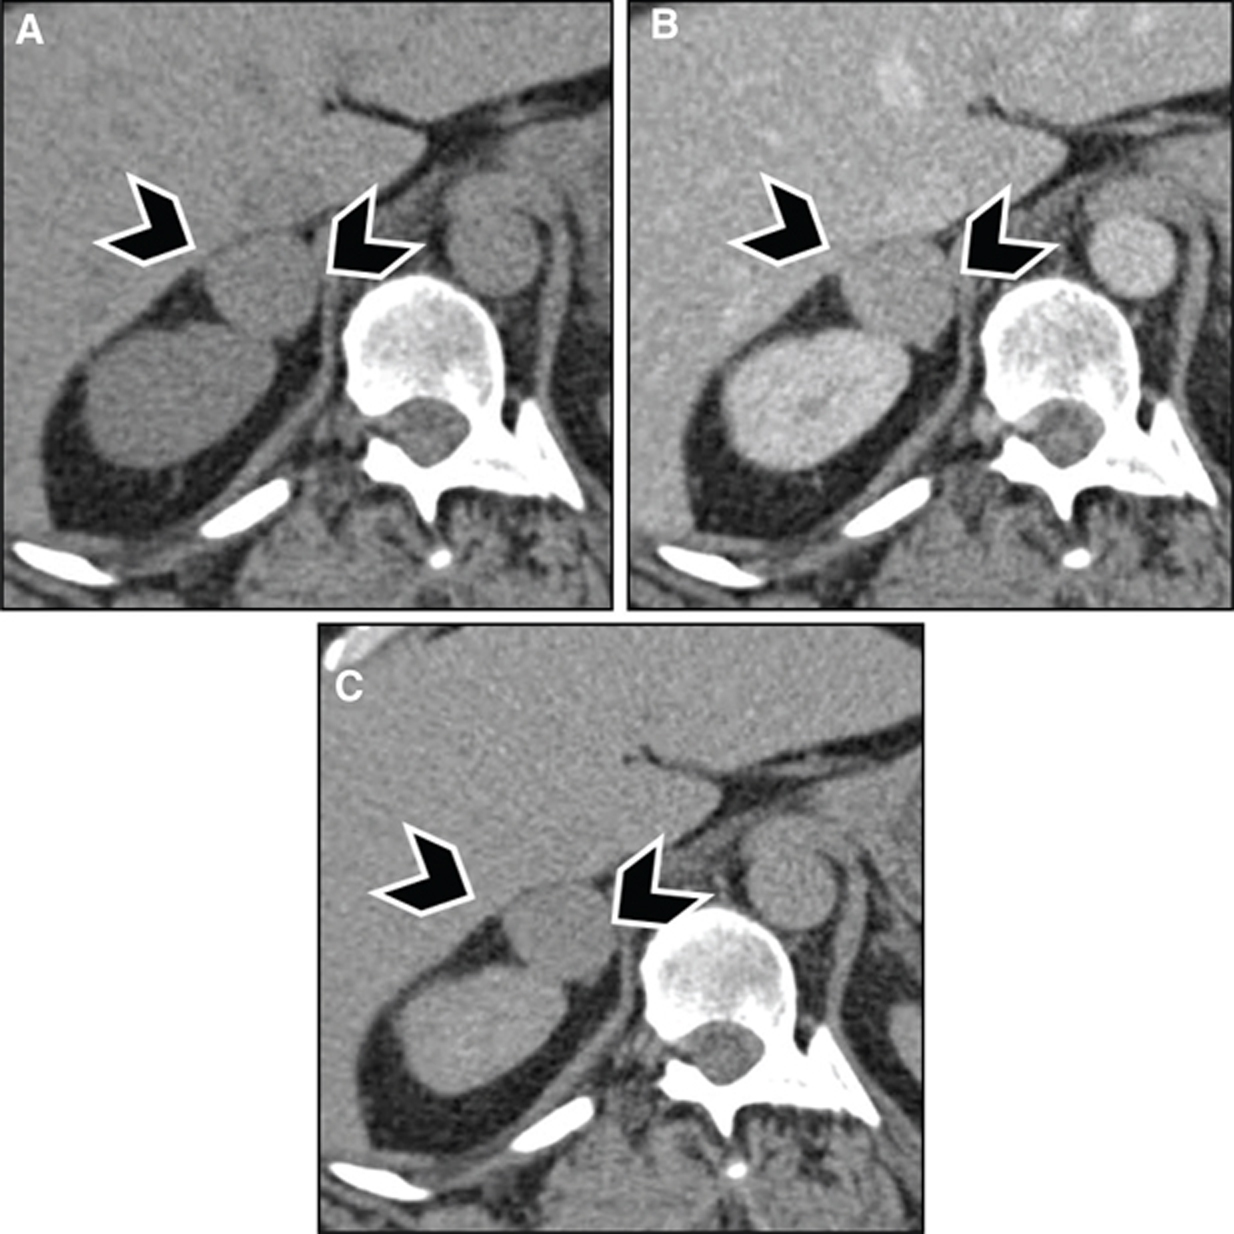

With contrast administration, PPGLs tend to enhance rapidly and avidly due to a rich capillary network (Figures 3 and 4). Adrenal adenomas usually demonstrate milder enhancement than pheochromocytomas or malignant tumors but have faster washout. Absolute washout of more than 60% or relative washout of more than 40% has been previously accepted as being characteristic of benign adrenal adenoma, although more recent studies have suggested that a good proportion of pheochromocytomas, potentially up to one-third, can have washout characteristics similar to benign adenomas (20, 21).

Fig 3

Figure 3 Pheochromocytoma in a 39-year-old male patient with neurofibromatosis type 1. (A) Noncontrast images demonstrate a hypodense lesion in the right adrenal gland (arrowheads), with (B) marked enhancement after contrast administration. (C) Adrenal washout phase acquired 15 min after contrast administration demonstrates rapid washout, which is usually seen with adrenal adenomas but can be seen in one-third of pheochromocytomas. The patient had elevated metanephrines, and surgical pathology was consistent with pheochromocytoma.